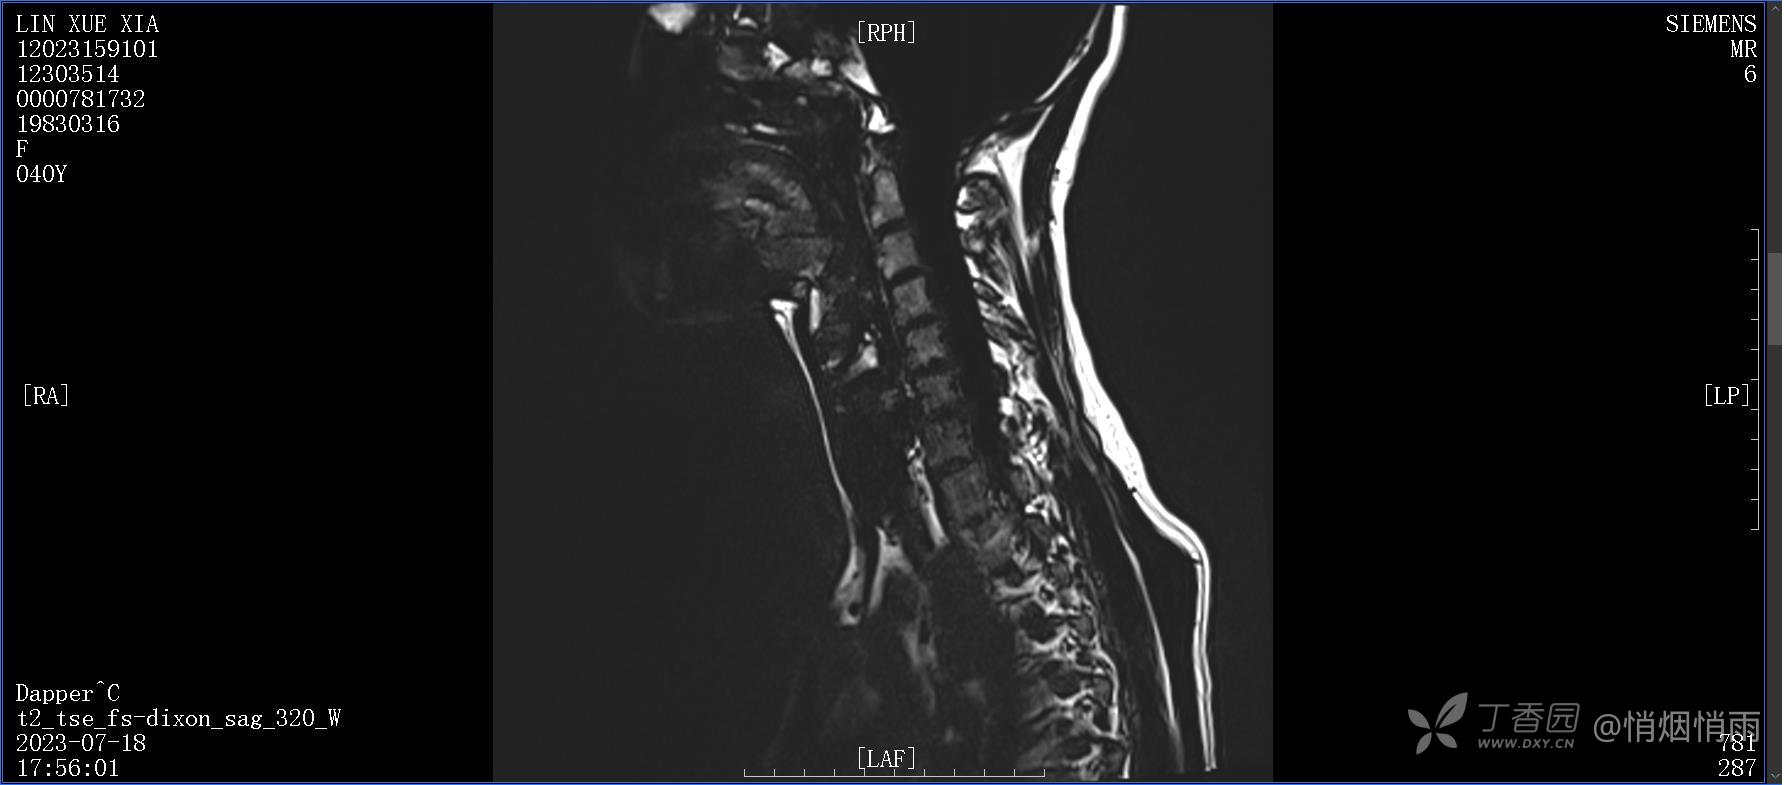

NeurothinkerZ 推荐患者女性,40岁,因右肩背部疼痛班活动受限4日余入院(2023-07-17)。

病史:入院前4天无明显诱因突然感右肩背疼痛伴随活动受限,自行口服依托考昔、艾瑞昔布等药物治疗,院外应用肩关节局部手法按摩等,均无明显改善。外院门诊诊为颈椎病。自诉既往多次“胸椎小关节紊乱”于当地诊所行手法按摩,治疗后好转,否认慢性疾病病史、外伤史、手术史,诉青霉素过敏,无其他药物食物过敏史,否认吸烟史、饮酒史,月经正常,经量正常。

查体:右肩关节局部轻度肿胀,肩胛区压痛明显,痛处不固定,肩关节痛性活动受限,jobe test(+),lift -off test(+),中指、环指感觉较余指减退,余肢端感觉及血运情况可。

目前的诊断,暂时依据辅助检查诊为肩袖损伤,但是患者疼痛的性质和特点,却不是单纯的肩袖损伤所致。考虑过胸廓出口综合征,但是该疾病会出现肩胛区的疼痛吗?(由于考虑到费用的问题,没再进行下一步的检查)带状疱疹会有如此的症状吗?